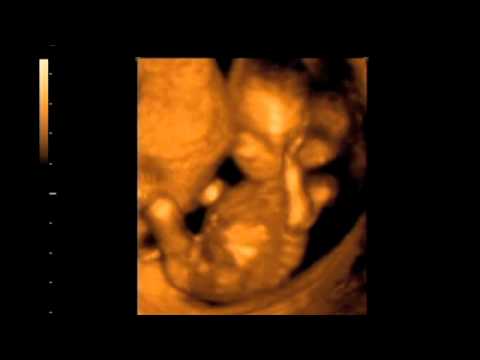

4D ultrasound 10 Weeks Moving And Jumping Clinica ...

The 3d 4d Ultrasound Experience at Goldenview Ultrasound Chicago, Boston,NYC &San Antonio - Duration: 4:29. GoldenViewUltrasound 1,440,454 views. 4:29 15 Weeks Gender Reveal 3D Ultrasound - Introducing NOAH MICHAEL VARGAS! - Duration: 3:20. Johnny Vargas 128,701 views. ... View Video

Neera Bhatia 3D Brochure Outside

San Antonio, TX 78212 (210) 222-2694 (210) 222-2565 www.neerabhatiaobgyn.com ultrasound with the added service of 3D/4D images of Neera_Bhatia_3D_Brochure_Outside Created Date: 8/14/2012 2:07:22 PM ... Access Doc